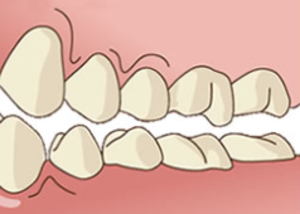

本来、上下の歯は、会話・食べ物の咀嚼・嚥下時に瞬間的に接触するだけです。1日の接触時間は、20分以下です。

唇を閉じていても、上下の歯は接触せずに2mm程空いている状態、舌は上顎にピッタリくっついている、これが正常です。

歯列不正(出っ歯、受け口、開口、叢生)